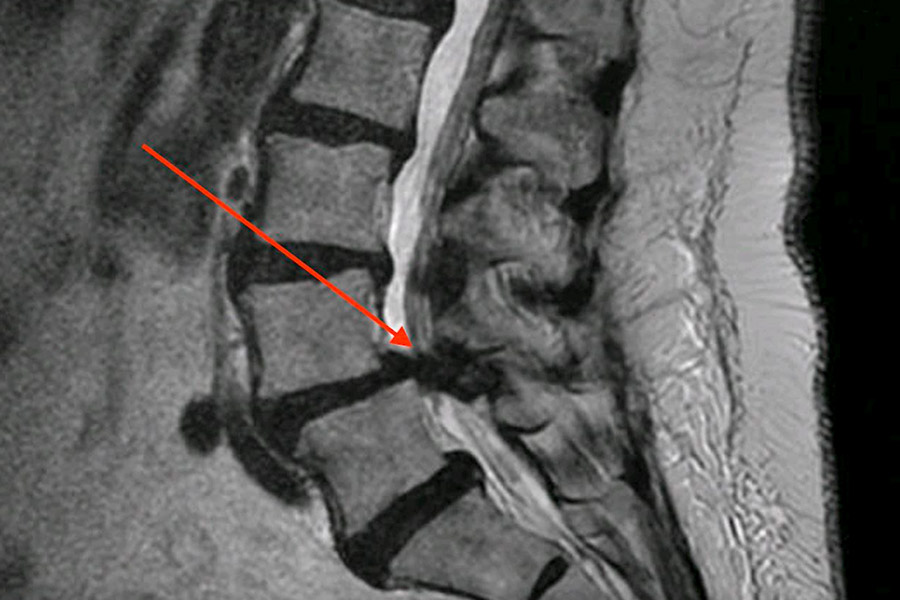

La paciente presentaba una estenosis lumbar debido a que la vértebra L4 sobre L5 se había desplazado ligeramente hacia delante, produciendo lo que se conoce como listesis. Además, también se había desarrollado una una hipertrofia del ligamento posterior.